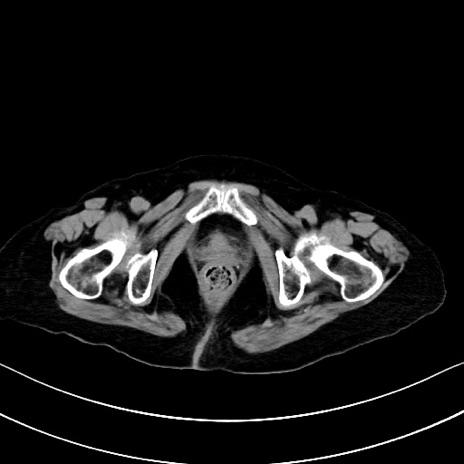

症例40(横断像)他院1日前

横断像